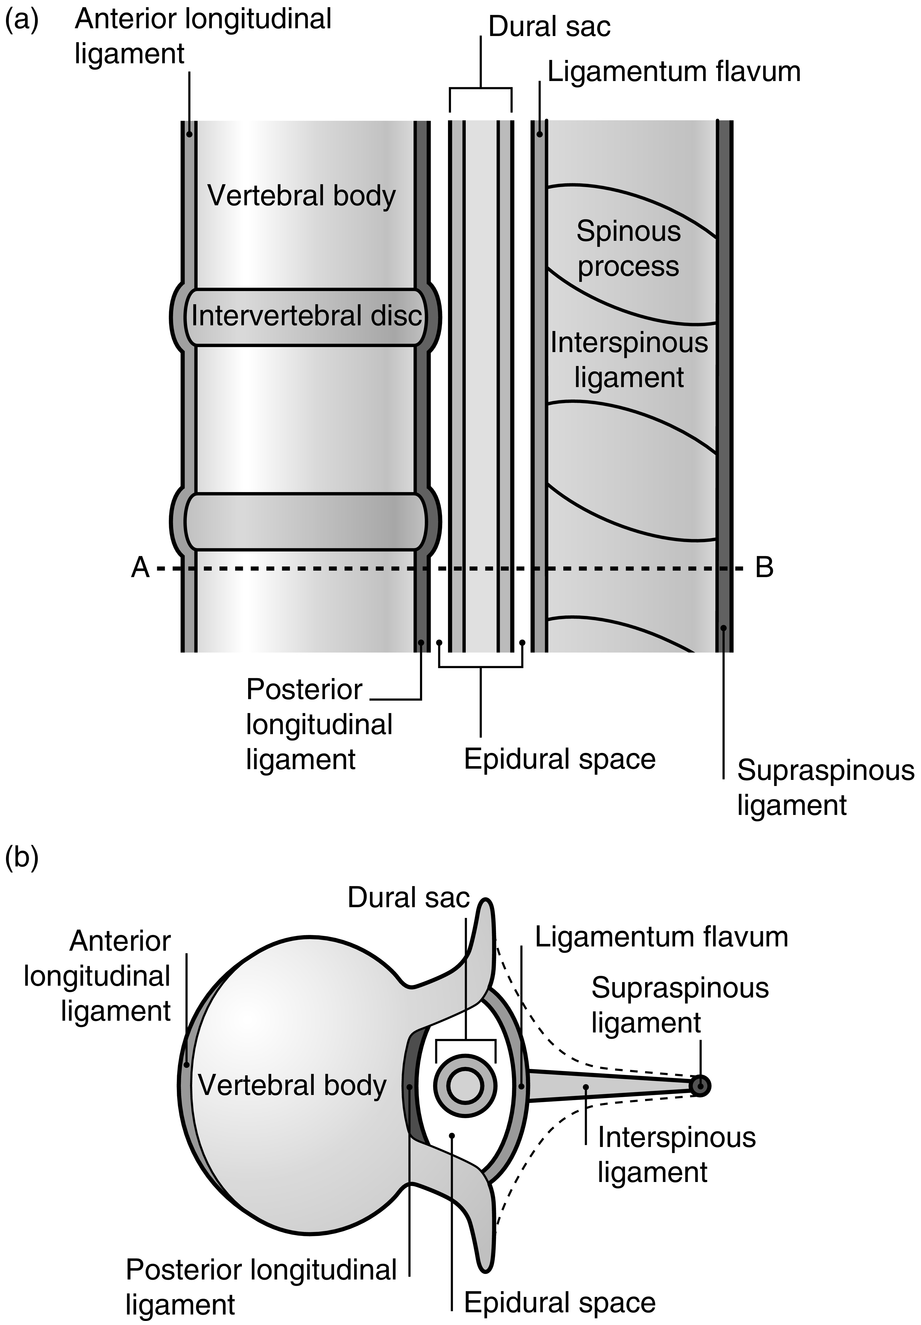

Anatomy of the vertebral column and spinal cord (Chapter 55) - Essential Clinical Anesthesia Review

The vertebral column usually contains three curves. The cervical and lumbar curves are convex anteriorly, and the thoracic curve is convex posteriorly. These curves, together with gravity, barricity of the local anesthetic,